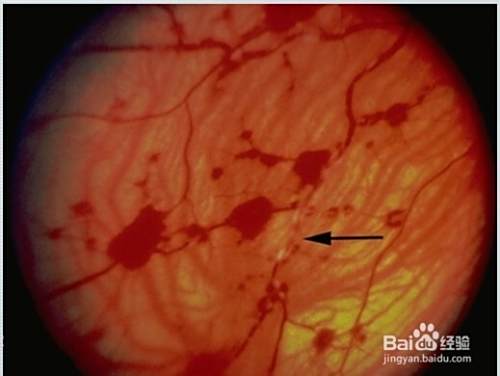

七:视网膜血管闭塞伴视网膜广泛出血。